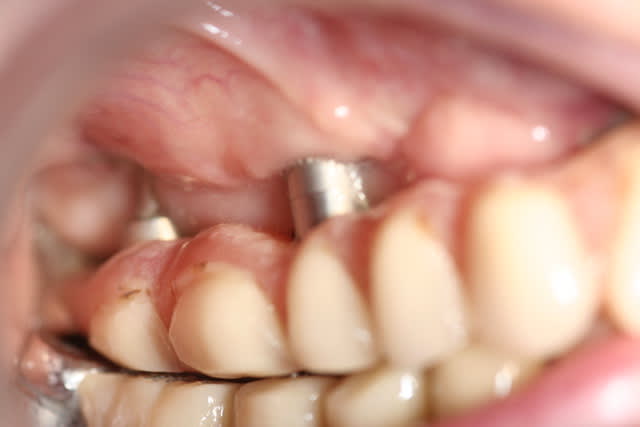

Je pense tenir le record du n'importe quoi implantaire.

> Je pense tenir le record du n'importe quoi implantaire.

petit bras

non content de le faire il l'enseigne, il a monter un DU pour cela

le cas a moins de deux ans, quand elle a mal il lui dit que c'est occlusal

j'ai refusé d'y mettre les doigts même avec des gants